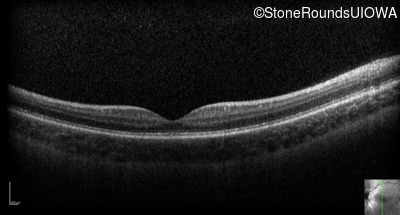

Optical Coherence Tomography - Right - 10/200 sc

Exemplar / OCT Stack

OCT Stack

Optical Coherence Tomography - Left - 10/200 sc